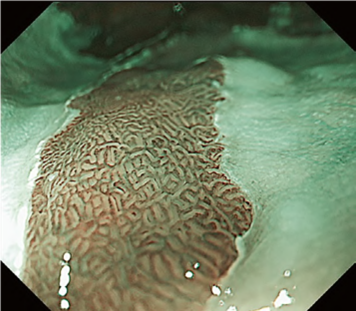

The flat pattern is a unique mucosal surface in BE showing an invisible/absent mucosal pattern, corresponding not to dysplastic but to non-dysplastic histology. The flat pattern was originally defined as invisible mucosal pattern (i.e., absence of pits and villi) with normal-appearing, long branching vessels. The flat pattern mimics an absent micro-surface (mucosal) pattern, which is significantly suggestive of early gastric cancer. As it was difficult for clinicians working in areas with a high incidence of gastric cancer to rate the flat pattern as non-dysplastic, recent studies proposed modified criteria for the “flat pattern.” This was to enhance the diagnostic accuracy for non-dysplastic lesions. This study used the modified criteria; according to these criteria, an invisible mucosal pattern without a distinct demarcation line and visible vascular patterns of long branching vessels or greenish thick vessels (GTV) was rated as “regular.” Thus, a flat pattern was rated as “regular” and the predicted histology as “non-dysplastic.” . Figure 3 shows representative NBI-M images of the flat pattern according to the modified criteria.

By using the diagnostic flowchart of the JES-BE classification (. Fig. 1), first, the mucosal pattern was classified as “visible” or “invisible” and rated as “regular” or “irregular” based on the diagnostic criteria for irregularity, as reported previously. The “invisible” mucosal pattern cannot be rated. Second, the vascular pattern was classified as “visible” or “invisible.” The “visible” vascular pattern included normal- appearing, long branching vessels and GTV previously reported and after- mentioned. General diagnosis was rated as “regular” or “irregular” based on mucosal plus vascular patterns. Finally, histology (“non-dysplastic” vs. “dysplastic”) was predicted according to the general diagnosis. “Dysplastic” corresponds to SBERN, including low-grade dysplasia (LGD), high-grade dysplasia (HGD), and superficial adenocarcinoma. Representative NBI-M images are shown in Fig. 4.